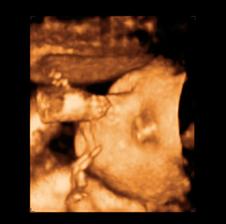

26 tt../1.4.2009/ naša paulínka je stráášne zlatá, boli sme si pozrieť na 4D utz. ..tvárila sa veľmi dôležito, až nafúkano...hehe..vôbec sa nechcela usmievať... nakoniec sa nám aj zasmiala...v brušku veľmi vyvádza, maminke dosť vytláča všetky časti telíčka, čo je niekedy aj dosť bolestivé...ale vydržíme, drobečkovi je tam určite tiež pritesno..a ešte aj stále viac a viac bude... strááášne sa na ňu tešíme🙂))